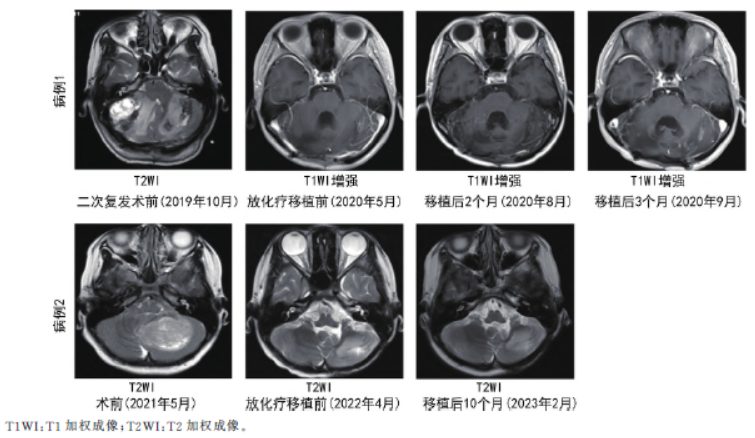

病例2,移植后12 d白细胞、16 d血小板植入。移植后第4、10个月多次行头颅及全脊柱MRI检查均提示未见肿瘤征象,目前持续随访中。两例患者治疗随访影像见图1。两例患者均未发生肝静脉闭塞症、严重肝肾功能不全、心肌损伤、严重出血等并发症。两例患者均出现Ⅰ~Ⅱ度口腔黏膜溃疡、腹泻

图1 两例MB患者不同治疗阶段MRI随访影像

病例1,移植后10 d白细胞、13 d血小板植入。移植后82 d(2020年8月31日)复查头颅MRI检查提示未见明显病灶。移植后104 d因左眼闭合不全、口角右斜来院就诊,复查头颅及全脊柱增强MRI提示双侧小脑半球多发强化影,颈4、5,腰2、5及骶1椎体水平椎管内多发结节状异常信号,考虑MB复发,伴肿瘤脑脊液播散可能。疗效评价:进展。后患者继续予以替莫唑胺、依托泊苷等药物治疗,移植后188 d(2020年12月15日)患者出现吞咽困难

伴进食呛咳,复查头颅及全脊柱MRI提示:桥脑池结节增大,椎管内病灶较前明显增大。遂放弃治疗出院。